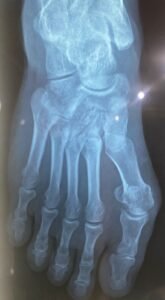

BANYUWANGI || Jejak-indonesia.id – Babak baru kasus dugaan kekerasan yang menimpa SHN kini semakin memanas setelah hasil medis resmi keluar. Penasehat hukum korban, Rozakki Muhtar, S.H., mengaku sangat terkejut saat mendampingi kliennya menjalani prosedur *rontgen* di rumah sakit.

Rozakki Muhtar saya tidak menyangka bahwa tindakan fisik yang diduga dilakukan oleh A.F, yang diketahui menjabat sebagai Direktur PT. Banyuwangi International Yacht (BIY), berdampak sangat fatal hingga menyebabkan struktur tulang kliennya mengalami kerusakan serius.

“Hingga hari ini, SHN mengaku masih merasakan nyeri luar biasa yang membuatnya kehilangan kemampuan gerak secara normal. Terhitung sudah sepuluh hari lamanya SHN tidak dapat bekerja atau menjalankan aktivitas produktif sebagaimana mestinya akibat cedera tersebut”Kata Rozakki Muhtar

Dalam hal tersebut kondisi ini menjadi poin krusial bagi tim hukum korban, karena hilangnya fungsi anggota tubuh untuk beraktivitas dalam jangka waktu lama merupakan parameter kuat adanya tindak pidana yang mengakibatkan luka berat.

Berdasarkan fakta medis patah tulang tersebut, Rozakki Muhtar menegaskan bahwa A.F tidak hanya terancam pasal penganiayaan biasa, tetapi berpotensi besar dijerat dengan pasal penganiayaan berat.

Fokus utama tim kuasa hukum kini adalah memastikan penyidik menggunakan hasil *rontgen* ini sebagai alat bukti primer untuk menahan pelaku. Dengan adanya bukti autentik patah tulang, unsur “luka berat” dalam KUHP telah terpenuhi, yang memiliki konsekuensi hukuman lebih lama. Selain itu, status A.F sebagai Direktur akan menjadi sorotan tajam bagi pihak Imigrasi untuk mengevaluasi keberadaan PT. BIY di Indonesia, mengingat adanya dugaan pelanggaran izin tinggal yang dibarengi dengan tindakan kriminal.